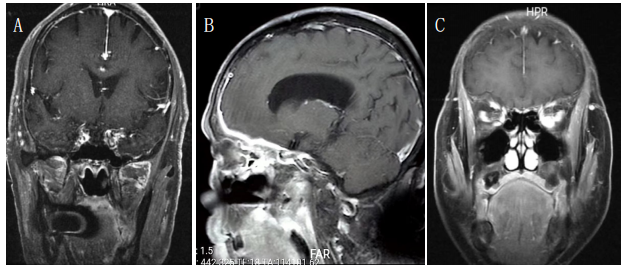

例6 患者,女性,60岁,因双眼复视、视力下降、视物变白前来求诊。既往甲状腺腺瘤行甲状腺部分切除。查体:双眼眼睑肿胀,眼球突出,结膜水肿,双眼各方向运动受限。实验室检验结果促甲状腺激素15.8 mU/L,游离三碘甲状腺原氨酸(FT3)正常、游离四碘甲状腺原氨酸(FT4)正常,眼眶MRI见双眼眼外肌增粗(图3A),参照2021年最新发布欧洲Graves'眼病专家组(EUGOGO)指南予甲泼尼龙500 mg连续6周及吗替麦考酚酯0.5 g、每日2次口服治疗后,双眼复视减轻,突眼、视力下降、视物变白均明显好转,3个月后复查,眼眶MRI见双侧眼外肌无明显增粗,双眼复视明显好转,无视物变白。

例7 患者,女性,20岁,表现为右眼上睑下垂,右眼外斜,定位在右侧动眼神经,头颅MRI示右侧动眼神经鞘瘤(图3B),患者病史多年,肿瘤生长缓慢,考虑手术治疗对症状无改善,未行手术治疗,建议定期复查。

例8 患者,男性,65岁,因眼球突出、双眼复视就诊。表现为无痛性双眼眼睑肿胀,眼球突出,结膜水肿,眼球运动受限,左侧显著,定位为眶内疾病,眼眶MRI表现为双侧眶内肿物(图3C)。眼眶软组织活检病理结果示右眼眶内B细胞淋巴瘤,免疫组织化学检查结果:CD20(+),CD79a(+),CD3(-),CD5(-),MUM-1(+),EBER原位杂交(-),CD23(残存生发中心+),TDT(-),Cmyc( + , 1 0 % ) , CD38( - ) , CD138( - ) ,SOX11(-),CyclinD1(-),CD10(-),Bcl-2(+),Bcl-6(+),Kappa(+),Lambda(-),Ki-67(阳性率约10%),符合结外黏膜相关淋巴组织边缘区淋巴瘤。转入血液科行环磷酰胺、阿霉素、长春新碱、泼尼松四种化疗药物治疗。

图 3 眼眶磁共振

Figure 3 Orbital MRI

(A) 例 6 ,TAO 患者,增强冠状面 T1WI 示双眼眼外肌增粗;(B) 例 7 右眼动眼神经鞘瘤患者,增强冠状面 T1WI 示右侧动眼神经鞘瘤;(C) 例 8 双眼眶 MALT 淋巴瘤患者,T2WI 脂肪抑制像横断面示双眼眶内肿物。

(A)Case 6, TAO patients, enhanced coronal T1WI showed bilateral extraocular muscle thickening; (B)Case 7: Right oculomotor neurilemmoma. Enhanced coronal T1WI showed right oculomotor neurilemmoma; (C)Case 8: Orbital MALT lymphoma, Cross section of T2WI fat suppression image showed orbital mass in both eyes.